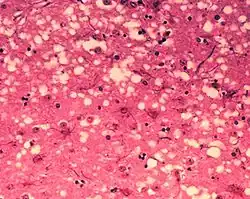

Прионы

Прионы — это инфекционные белковые молекулы, не содержащие ДНК или РНК[61]. Они вызывают такие заболевания, как почесуха овец[62], губчатая энцефалопатия крупного рогатого скота и хроническая слабость (англ. chronic wasting disease) у оленей. К прионным болезням человека относят куру, болезнь Крейтцфельдта — Якоба и синдром Герстмана — Штраусслера — Шейнкера[63]. Прионы способны стимулировать образование собственных копий. Прионный белок способен существовать в двух изоформах: нормальной (PrPC) и прионной (PrPSc). Прионная форма, взаимодействуя с нормальным белком, способствует его превращению в прионную форму. Хотя прионы фундаментально отличаются от вирусов и вироидов, их открытие даёт больше оснований поверить в то, что вирусы могли произойти от самовоспроизводящихся молекул[64].